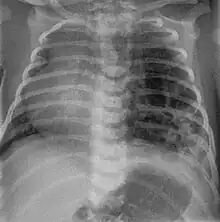

CPAMs are often identified during routine prenatal ultrasonography. Identifying characteristics on the sonogram include: an echogenic (bright) mass appearing in the chest of the fetus, displacement of the heart from its normal position, a flat or everted (pushed downward) diaphragm, or the absence of visible lung tissue.

CPAMs are classified into three different types based largely on their gross appearance. Type I has a large (>2 cm) multiloculated cysts. Type II has smaller uniform cysts. Type III is not grossly cystic, referred to as the "adenomatoid" type. Microscopically, the lesions are not true cysts, but communicate with the surrounding parenchyma. Some lesions have an abnormal connection to a blood vessel from an aorta and are referred to as "hybrid lesions."

Imaging

The earliest point at which a CPAM can be detected is by prenatal ultrasound. The classic description is of an echogenic lung mass that gradually disappears over subsequent ultrasounds. The disappearance is due to the malformation becoming filled with fluid over the course of the gestation, allowing the ultrasound waves to penetrate it more easily and rendering it invisible on sonographic imaging. When a CPAM is rapidly growing, either solid or with a dominant cyst, they have a higher incidence of developing venous outflow obstruction, cardiac failure and ultimately hydrops fetalis. If hydrops is not present, the fetus has a 95% chance of survival. When hydrops is present, risk of fetal demise is much greater without in utero surgery to correct the pathophysiology. The greatest period of growth is during the end of the second trimester, between 20–26 weeks.

A measure of mass volume divided by head circumference, termed cystic adenomatoid malformation volume ratio (CVR) has been developed to predict the risk of hydrops. The lung mass volume is determined using the formula (length × width × anteroposterior diameter ÷ 2), divided by head circumference. With a CVR greater than 1.6 being considered high risk. Fetuses with a CVR less than 1.6 and without a dominant cyst have less than a 3% risk of hydrops. After delivery, if the patient is symptomatic, resection is mandated. If the infant is asymptomatic, the need for resection is a subject of debate, though it is usually recommended. Development of recurrent infections, rhabdomyosarcoma, adenocarcinomas in situ within the lung malformation have been reported.[4]